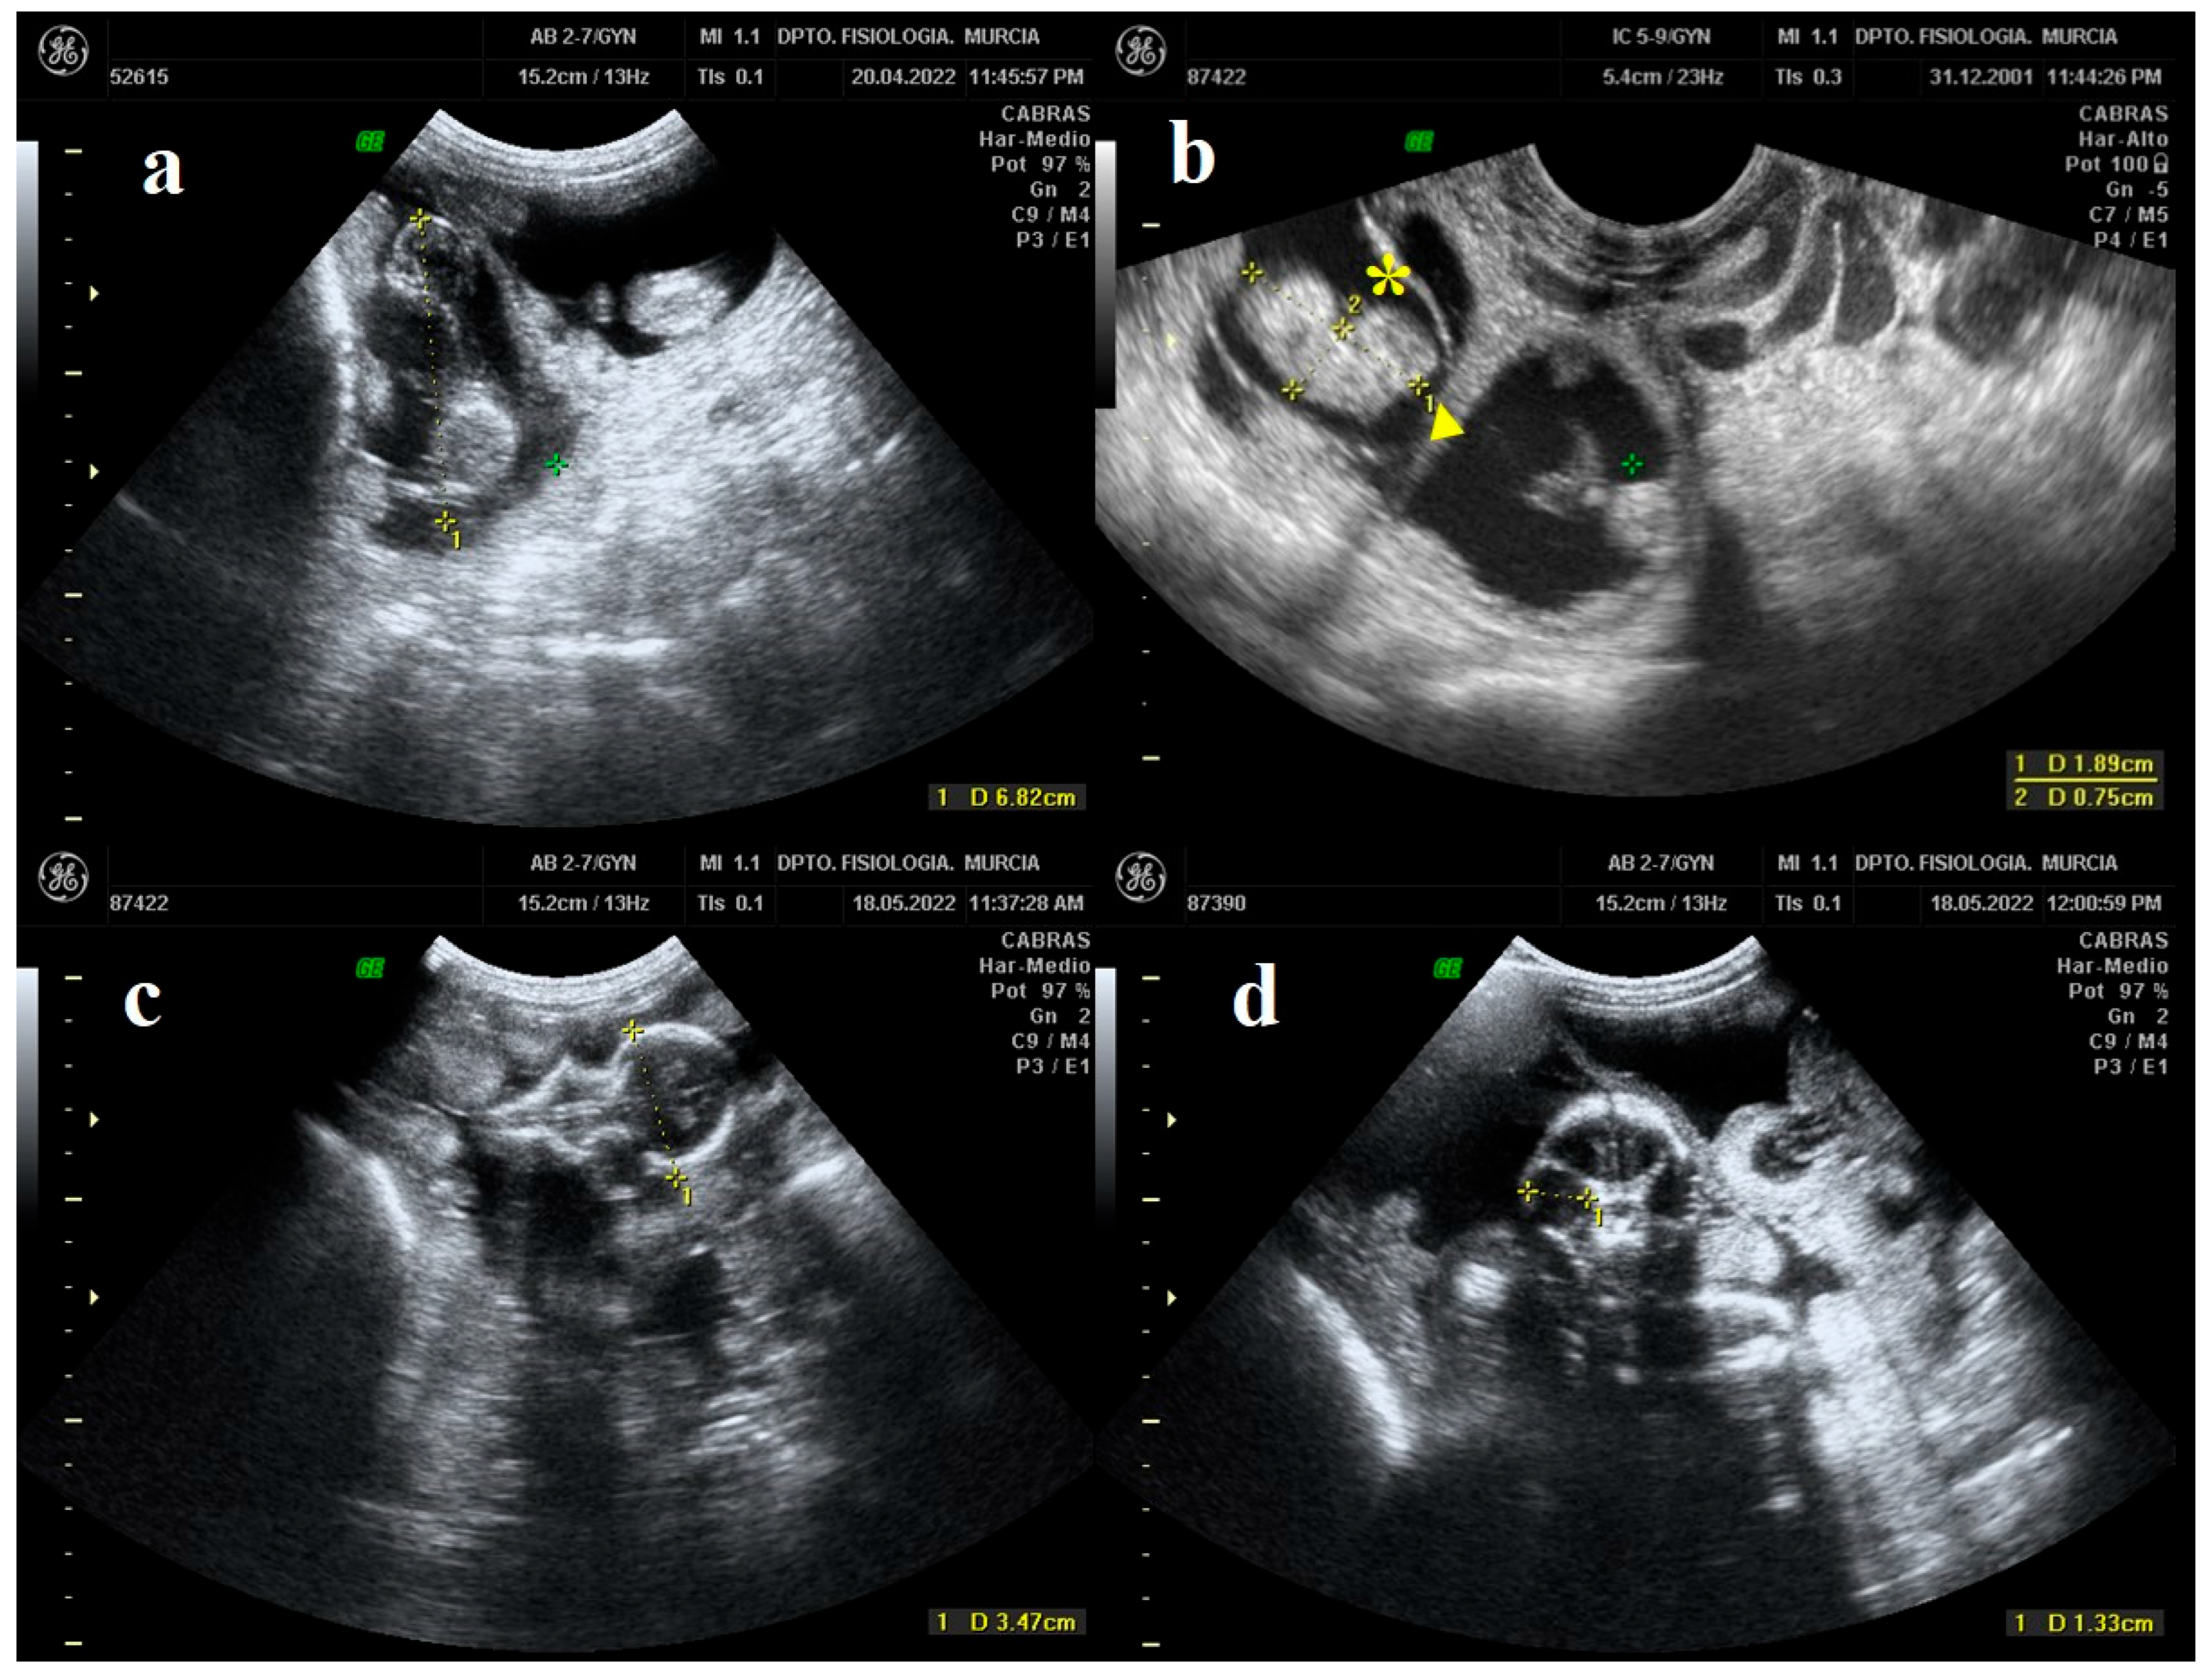

Crown-rump length (CRL) has been proven as a common and reliable measure to determine biometric parameters in fetuses during the first third of pregnancy [36]. Measurements were taken from the highest part of the skull to the end of the sacrum (Figure 1a) [37]. On the other hand, the trunk diameter (TD) is the maximum diameter of the fetal body measured from the vertebral column to the ventral portion of the abdomen (Figure 1b) [19].

Figure 1.

B-mode ultrasound images in which fetal growth indices are measured. (a) The yellow line represents the crown-rump length (CRL). (b) The yellow line marked with (▶) represents the crown-rump length (CRL) and the one marked with (*) represents the trunk diameter (TD). (c) The yellow line represents the biparietal diameter (BPD). (d) The yellow line represents the eye orbit diameter (EOD).

The biparietal diameter (BPD) is a measurement that is routinely performed in the prenatal examination of pregnancy to estimate the birth date in several goat breeds. For its measurement, a symmetrical view of the fetal skull must be obtained. When looking at the maximum oval-shaped size of the skull (looking at both eye sockets from the front), BPD was measured from one parietal end to the other (Figure 1c) [14]. Finally, the measurement of the eye orbit diameter (EOD) must be taken once it is observed to have a rounded shape at its maximum size, thus measuring the diameter of the circle formed (Figure 1d) [14].